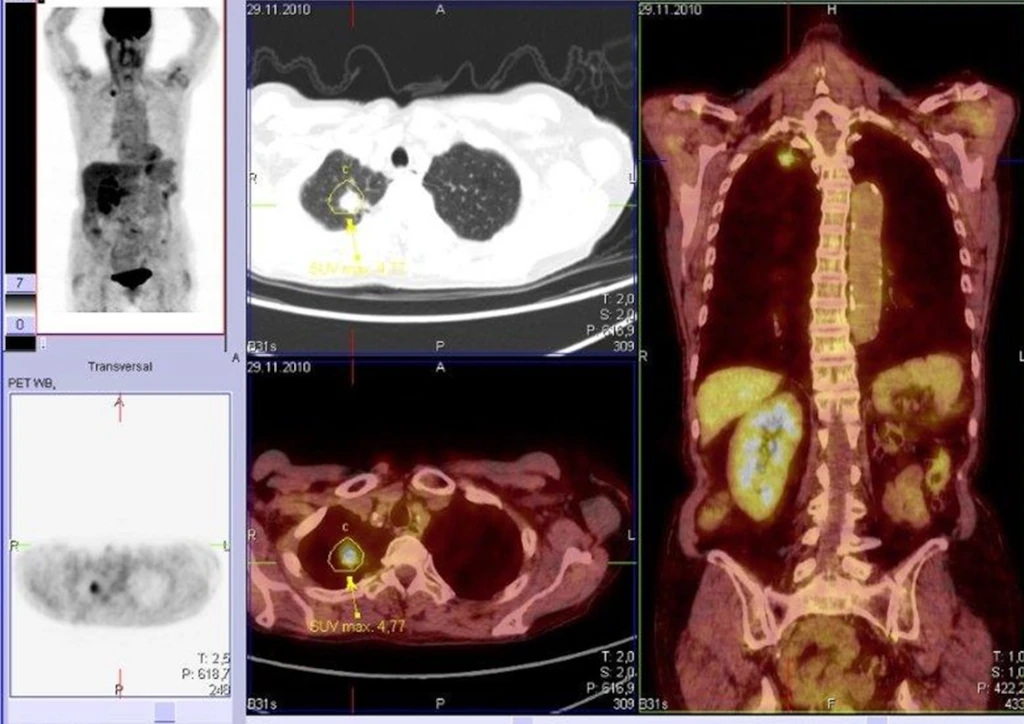

PET-CT eines bösartigen Lungenherdes

Die PET-CT ist eine Kombination aus 2 unterschiedlichen bildgebenden Untersuchungsverfahren, nämlich der Positronen-Emissions-Tomographie (PET) und der Computertomographie (CT).

Mittels radioaktiv markiertem Traubenzucker (FDG) oder anderer PET-Tracer können Stoffwechselvorgänge im Körper sichtbar gemacht werden.